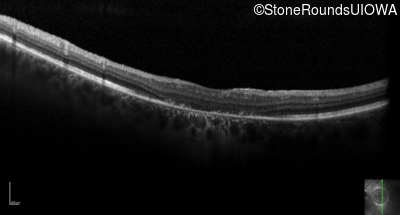

Optical Coherence Tomography - Left - 10/160 sc

Exemplar / OCT Stack